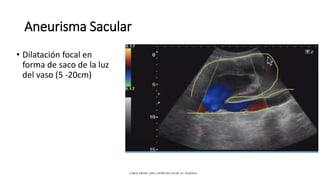

Aneurisma Sacular

• Dilatación focal en

forma de saco de la luz

del vaso (5 -20cm)